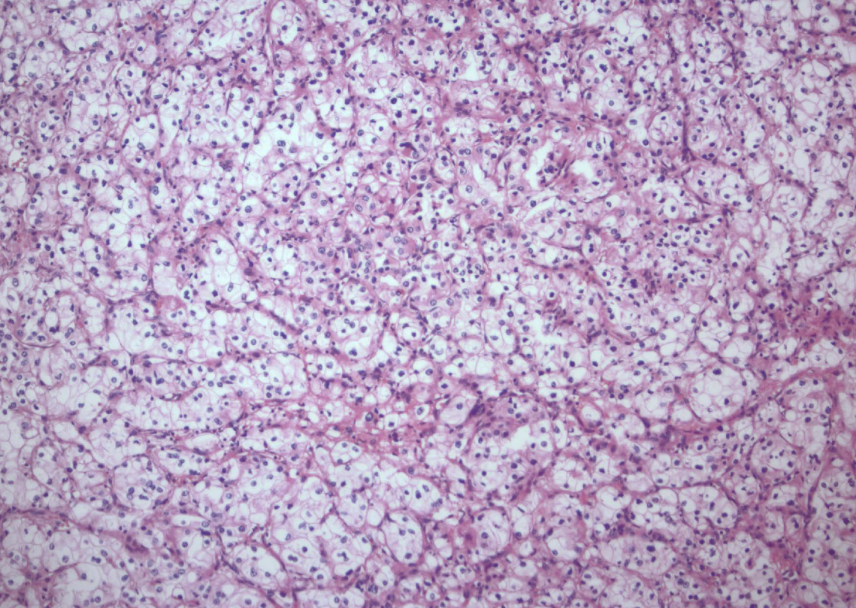

clear cell RCC

clear cell RCC

clear cell RCC

glycogen and lipid cytoplasm with rich vascular network